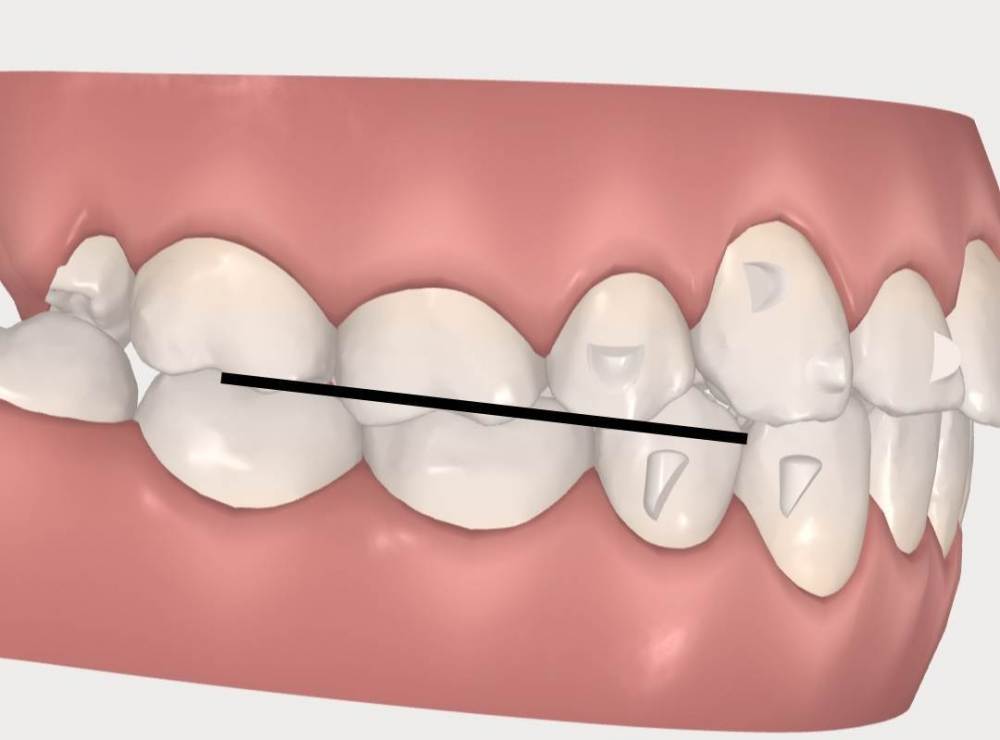

АнтонТЛТ Опубликовано 5 января, 2022 Поделиться Опубликовано 5 января, 2022 Задние бугры верхнего левого первого моляра находятся ниже уровня где они должны быть, это связано с выдвижением зуба из-за длительного наклона нижнего левого первого моляра. Так же этот верхний зуб находится в более нёбном положении относительно соседних зубов. Ссылка на комментарий

АнтонТЛТ Опубликовано 5 января, 2022 Поделиться Опубликовано 5 января, 2022 (изменено) Если провести воображаемую линию по режущим краям передних зубов и по щечным буграм жевательных зубов верхней челюсти то должна получиться элиптическая линия без ступенек, в Вашем случае не все зубы довернуть. Изменено 5 января, 2022 пользователем АнтонТЛТ 1 Ссылка на комментарий

АнтонТЛТ Опубликовано 5 января, 2022 Поделиться Опубликовано 5 января, 2022 (изменено) Нижняя челюсть должна иметь параболическую форму. Видно, что нижний левый первый моляр находится в более язычном положении, его наклон в передне-заднем направлении исправили, но наклон в щечно-язычном направлении остался. Нижний правый второй моляр тоже расположен более язычно по сравнению с соседними зубами. Изменено 5 января, 2022 пользователем АнтонТЛТ Ссылка на комментарий